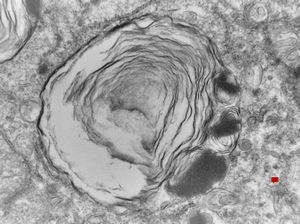

M,22y. | alveolar macrophage … phagocytosed surfactant